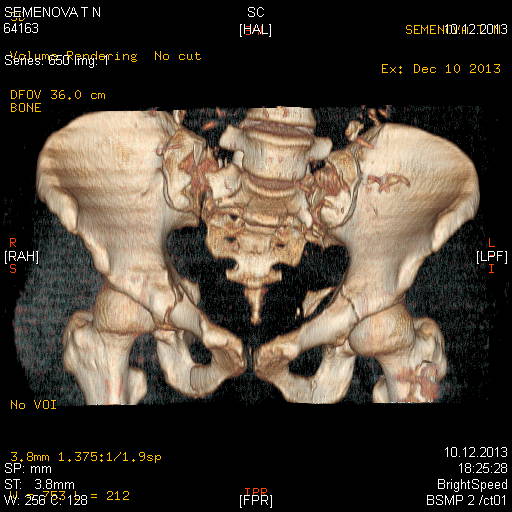

Доброго времени суток коллеги! Прошу вас подсказать тактику в решении оперативного лечения следующего сложного повреждения таза. Был ли опыт в фиксации подобных повреждений? Травма 03.12.2013,больная переведена из лечебного учреждения соседней области.На данный момент у больной следующий диагноз: ЗЧМТ,сотрясение головного мозга;Закр. травма грудной клетки,множественные переломы ребер справа с повреждением ткани легкого,правосторонний гемопневмоторакс,состояние после торакоцентеза;Закр.травма живота,разрыв селезенки,гемоперионеум, состояние после лапаротомиии спленэктомии;Закр. оскольчатый перелом сред-верх\3 левой бедренной кости, состояние после накостного металлостеосинтеза; Закр.поперечный переломовывих на уровне S1S2, многооскольчатый перелом латеральных масс крестца с обеих сторон,перелом обеих лонных и седалищных костей. Перелом поперечных отростков L1,L2,L3,L4, L5 позвонка. ШОК 3ст. Вкратце изложил диагноз. В настоящее время состояние больной тяжелое. Первым этапом планируем наложить АНФ (переднюю раму) После стабилизации состояния необходимо будет выполнить фиксацию: . Имеется один вопрос - какие импланты необходимы т.е. в какой комбинации и какая последовательность фиксации?

Добрый день! Станислав! Повреждение таза действительно тяжелое. В данном случае по мимо перелома передних колонн, что не самое страшное, имеется H-образный перелом крестца со смещением каудальной части. перелом поперечных отростков подтверждает вертикально нестабильный характер травмы таза. Предложенная конструкция действительно является вариантом решения проблемы,а скомпоновать ее можно из любого транспедикулярного фиксатора той фирмы которая работает у вас с нейрохирургами.Но помимо этого необходимо выполнить декомпрессию корешков конского хвоста. в противном случае та неврология которая есть и сейчас останется на всю жизнь. Судя по тяжести состояния к лечению перелома крестца сможете приступить не скоро, скорее всего на данный момент доминирует легочный дисстресс синдром, наверняка есть анемия после гемопневмоторакса, лапаротомии и накостного остеосинтеза бедренной кости.Поэтому когда дойдет дело до крестца репонировать отломки будет весьма сложно. Мы бы начали с остеосинтеза ребер, чтобы сделать пациента мобильным, передние колонны можно фиксировать перкутанно винтами, сзади кроме илиолюмбальной конструкции, ляминэктомия с целью декомпрессии, репозиция и дополнительная фиксация реконструктивными пластинами, лучше LCP. Пригласите на операцию нейрохирурга-вертебролога. Успехов.

При переломо-вывихах крестца неврологический статус является одним из основных показаний к оперативному лечению. Наличие неврологических симптомов ускоряет процесс, и проблему надо решить ургентно в первые дни..

Для фиксации крестца предложены различные методы и представленный снимок является одним из примеров. Если местные возможности позволяют, и имеются специалисты, знающие методы, которые помогут создать эстетичную фиксацию, надо этим воспользоваться. Но ради красивой картины не стоит жертвовать неизвестной для вас методикой.

В данном случае кроме фиксации крестца требуется декомпрессия канала. А вправленный вывих надо удержать, и вертикальные пластины с юникортикальной возможностью в 2.7 мм помогут создать стабильность. Кроме этого, надо создать условия по предупреждению компрессии крестца с двух сторон. В связи с тем, что процедура заканчивается в области крестца, а также наличие повреждения позвонков, это ограничивает возможности педикулярной фиксации. Мне кажется, от боковой компрессии лучше удержала бы согнутая по контуру крыла узкая в 4.5 мм балка-пластина.